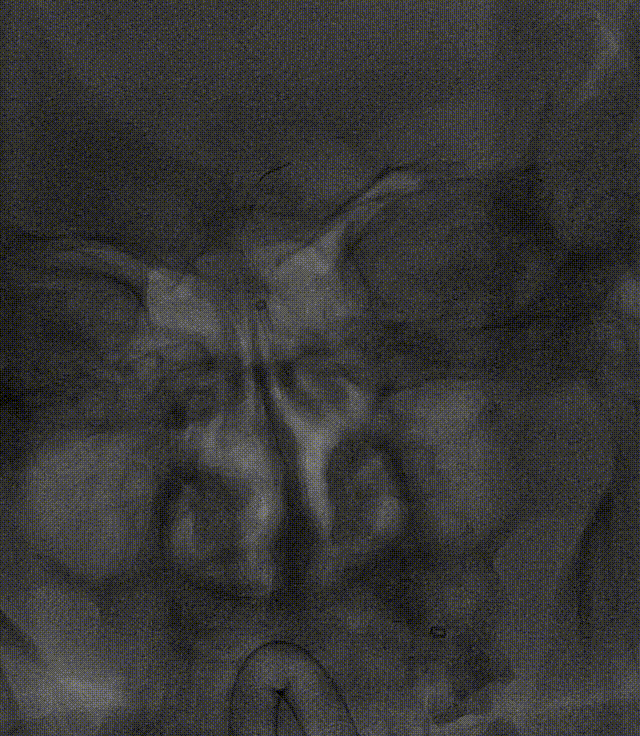

运用BASIS技术植入3.0*25mm Syphonet®取栓支架,输送球囊对闭塞段进行扩张。

运用BASIS技术回收3.0*25mm Syphonet®取栓支架及5F 125cm Tethys®中间导引导管,取出血栓;

复查造影:左侧椎动脉、双侧大脑后动脉、小脑上动脉、小脑前下动脉显影正常。